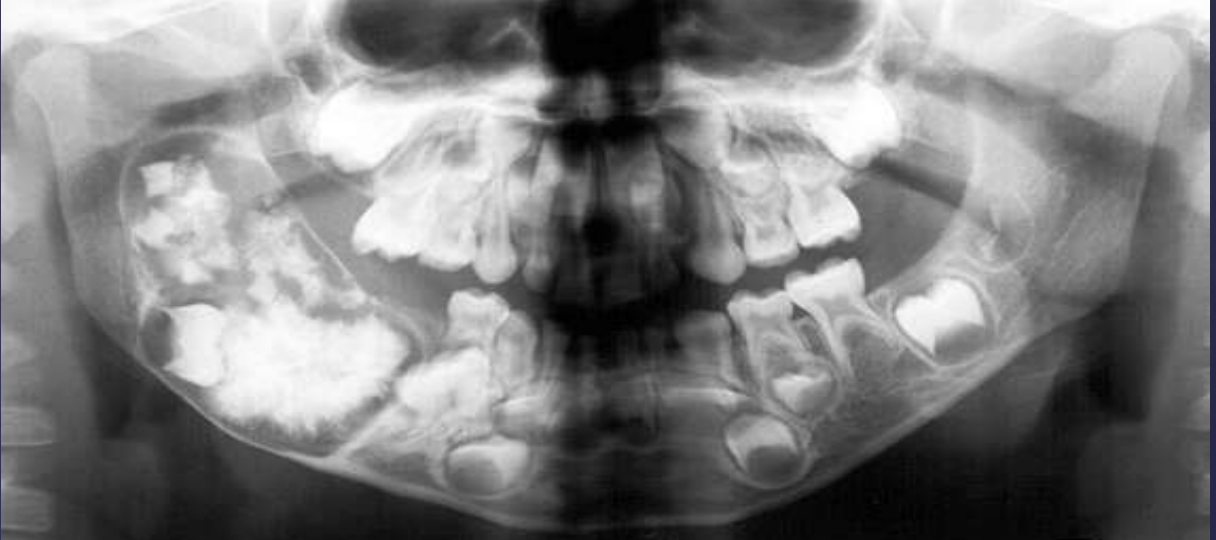

what is the #1 most common odontogenic tumor/hamartoma?

odontoma

• 74% of odontogenic tumors in USA

COMPOUND odontomas

• Well defined, corticated

• Radiolucent band/soft tissue capsule inside the cortical border

• Internal content is largely radiopaque- made of multiple tooth like structures called denticles

• Maybe be associated with unerupted tootH

COMPLEX odontomas

Well defined, corticated

Radiolucent band/soft tissue capsule inside the cortical border

Internal content is largely radiopaque- made of irregular mass of calcified tissue

Maybe be associated with unerupted tooth

Possible displacement of teeth (30, 29)

Compound –Complex Odontoma

Well defined

Mixed density, corticated

Combination of amorphous radiopaque mass and tooth like structures

Osseous expansion

Thinning of cortices

Displacement of teeth, unerupted tooth